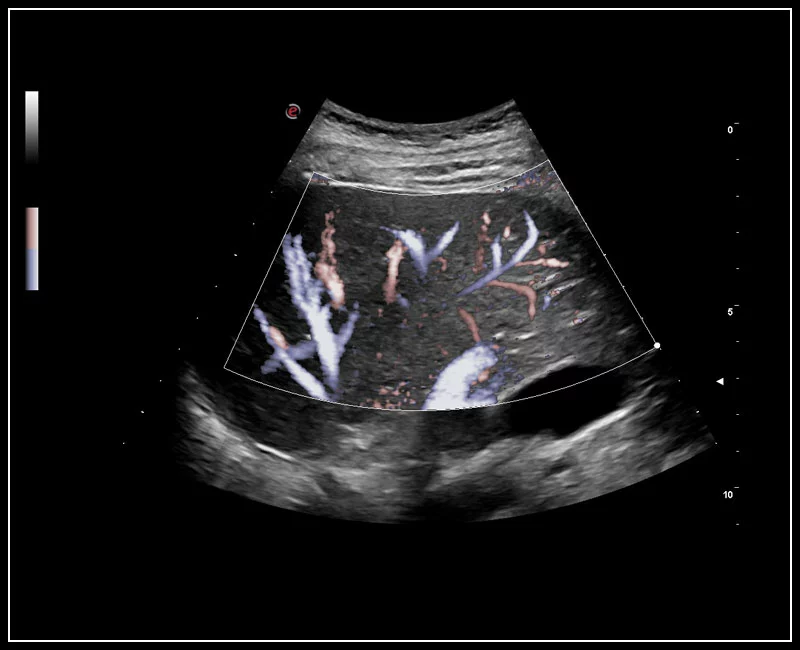

MyLab™9 Platform - XFlow Doppler enhancement in liver vascularization

MyLab™9 Platform - XFlow Doppler enhancement in liver vascularization